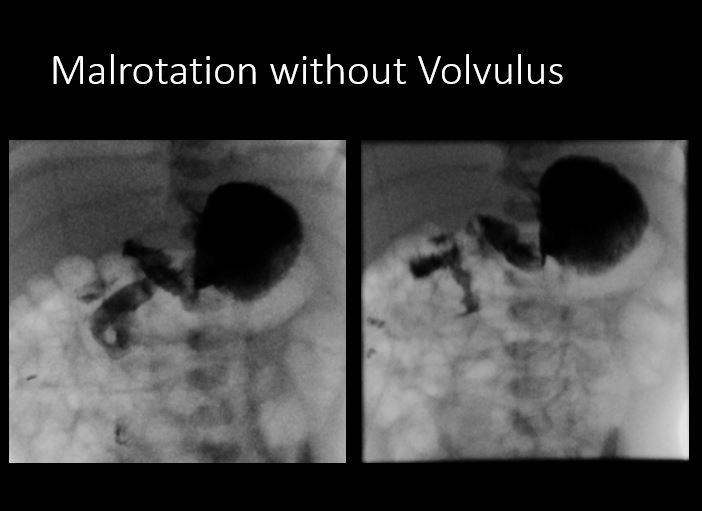

Pediatric Fluoroscopic Upper Gastrointestinal Series

Findings

Scout Image of the abdomen